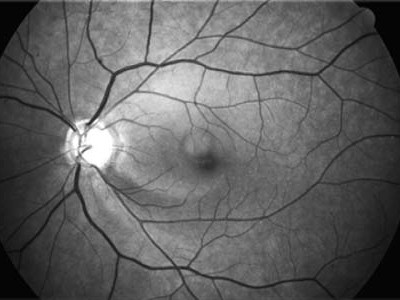

Barevná fotografie

Barevná fotografie věrně reprodukuje barevnost papily Digitální snímek vrstvy nervových vláken

/digitální snímky zrakového nervu, vrstvy nervových vláken/

má své stálé a nezastupitelné místo, neboť věrně reprodukuje barevnost papily a jejího okolí, je schopna zachytit hemorhagie na rozdíl od konfokální skenovací laserové oftalmoskopie /HRT/ nebo spektrální optické koherentní tomografie /SOCT/. Snímky vrstvy nervových vláken z funduskamery mají velkou senzitivitu i pro jemné výpadky ve vrstvě nervových vláken a to i ve větší vzdálenosti od papily.